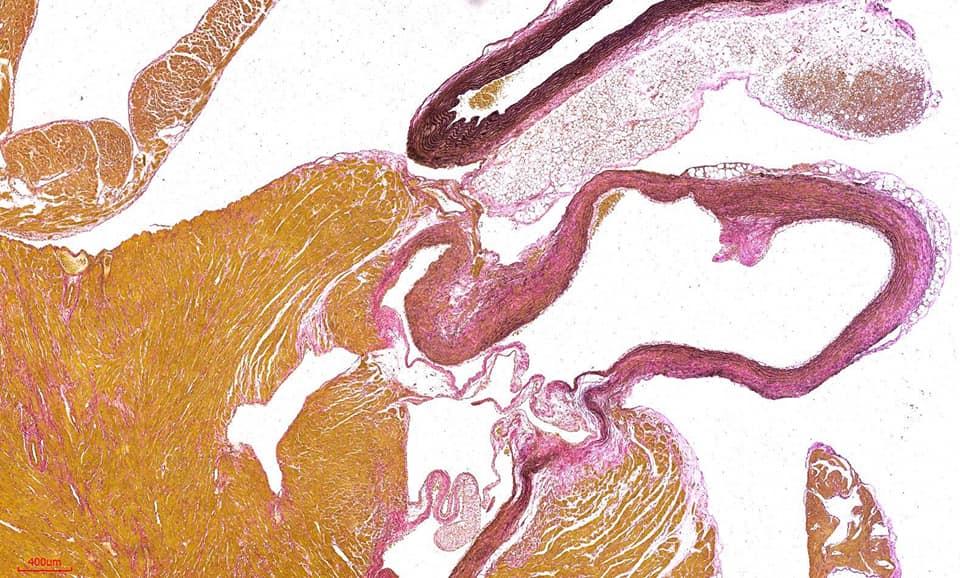

彈力纖維(Verhoeff’s Van Gieson,EVG)染色,彈性纖維廣泛分佈與身體各處,特別在動脈壁、肺泡壁和皮膚中最為豐富。觀察組織內彈性纖維是否有增生或斷裂崩解等。

Miller’s Elastic Stain ( E.V.G stain) 實際染色範例

※結果觀察:

彈力纖維呈藍黑色,肌纖維、纖維素、神經膠質呈黃色,膠原纖維呈紅色,胞核呈藍色